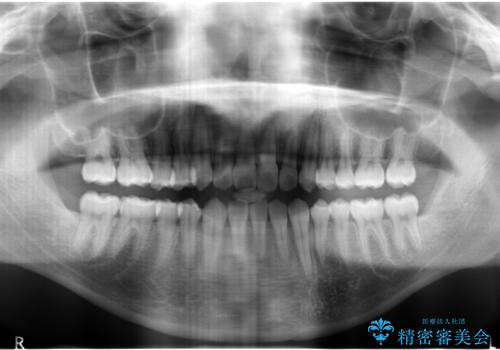

- 前歯のガタガタを主訴に来院。

下の前歯は一本保険治療での被せ物になっており、変色していました。

・神経のない下の前歯を残す

・神経のない歯を抜いてしまって、天然歯で閉じる

のプランを提案し、神経のない前歯を抜く選択をされました。

下の前歯が3本になり奇数になることで、上下の真ん中は一致しませんが、そこまで目立たないと思います。

残りは全て天然歯になり、人工物の心配をしなくて済むようになりました。

下の前歯の歯槽骨が一番薄く、歯肉退縮のリスクがあるため、今回のような1本抜歯も選択肢の一つです。